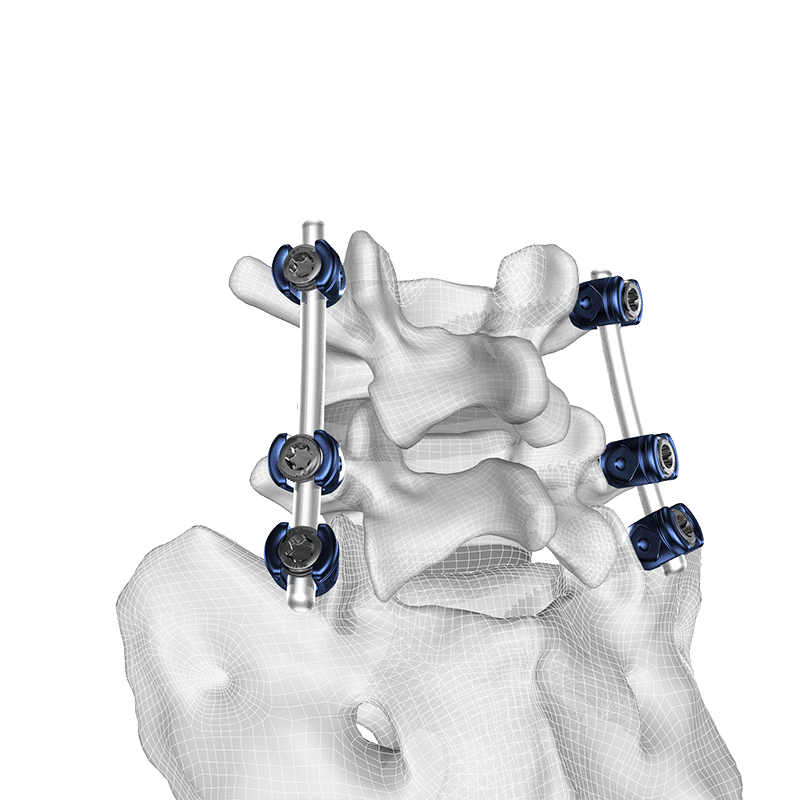

Tiger® Pedicle Screw System

The Tiger Spine fixation system offers a comprehensive variety of implant and instrument options to build constructs from ilium to occiput.

Product Features

- Constant helix angle thread for maximized pullout resistance

- Polyaxial, monoaxial, uniplanar, fracture, & reduction screws

- 4 methods of rod reduction

- 60° cone of screw angulation